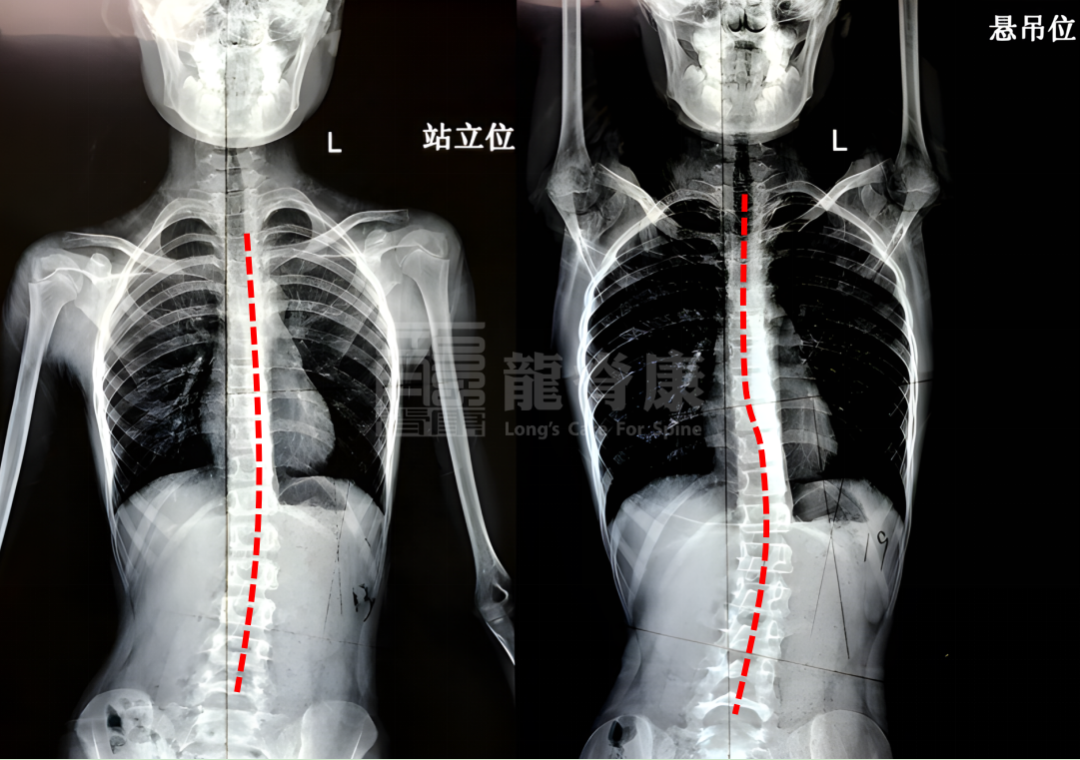

吊单杠对侧弯患者

有什么影响呢?

当孩子手握单杠悬吊时,更多是对矢状面的位置产生拉直作用,而对冠状面的侧弯度数改善不大。并且,带有旋转的椎体可能会导致关节小关节卡住,此时若一味地向下拽拉,会使小关节越卡越紧,不仅无法得到松解,还可能加重疼痛。

所以,对于特发性脊柱侧弯或弯曲的患者,单纯依靠吊单杠进行运动治疗并不合适。